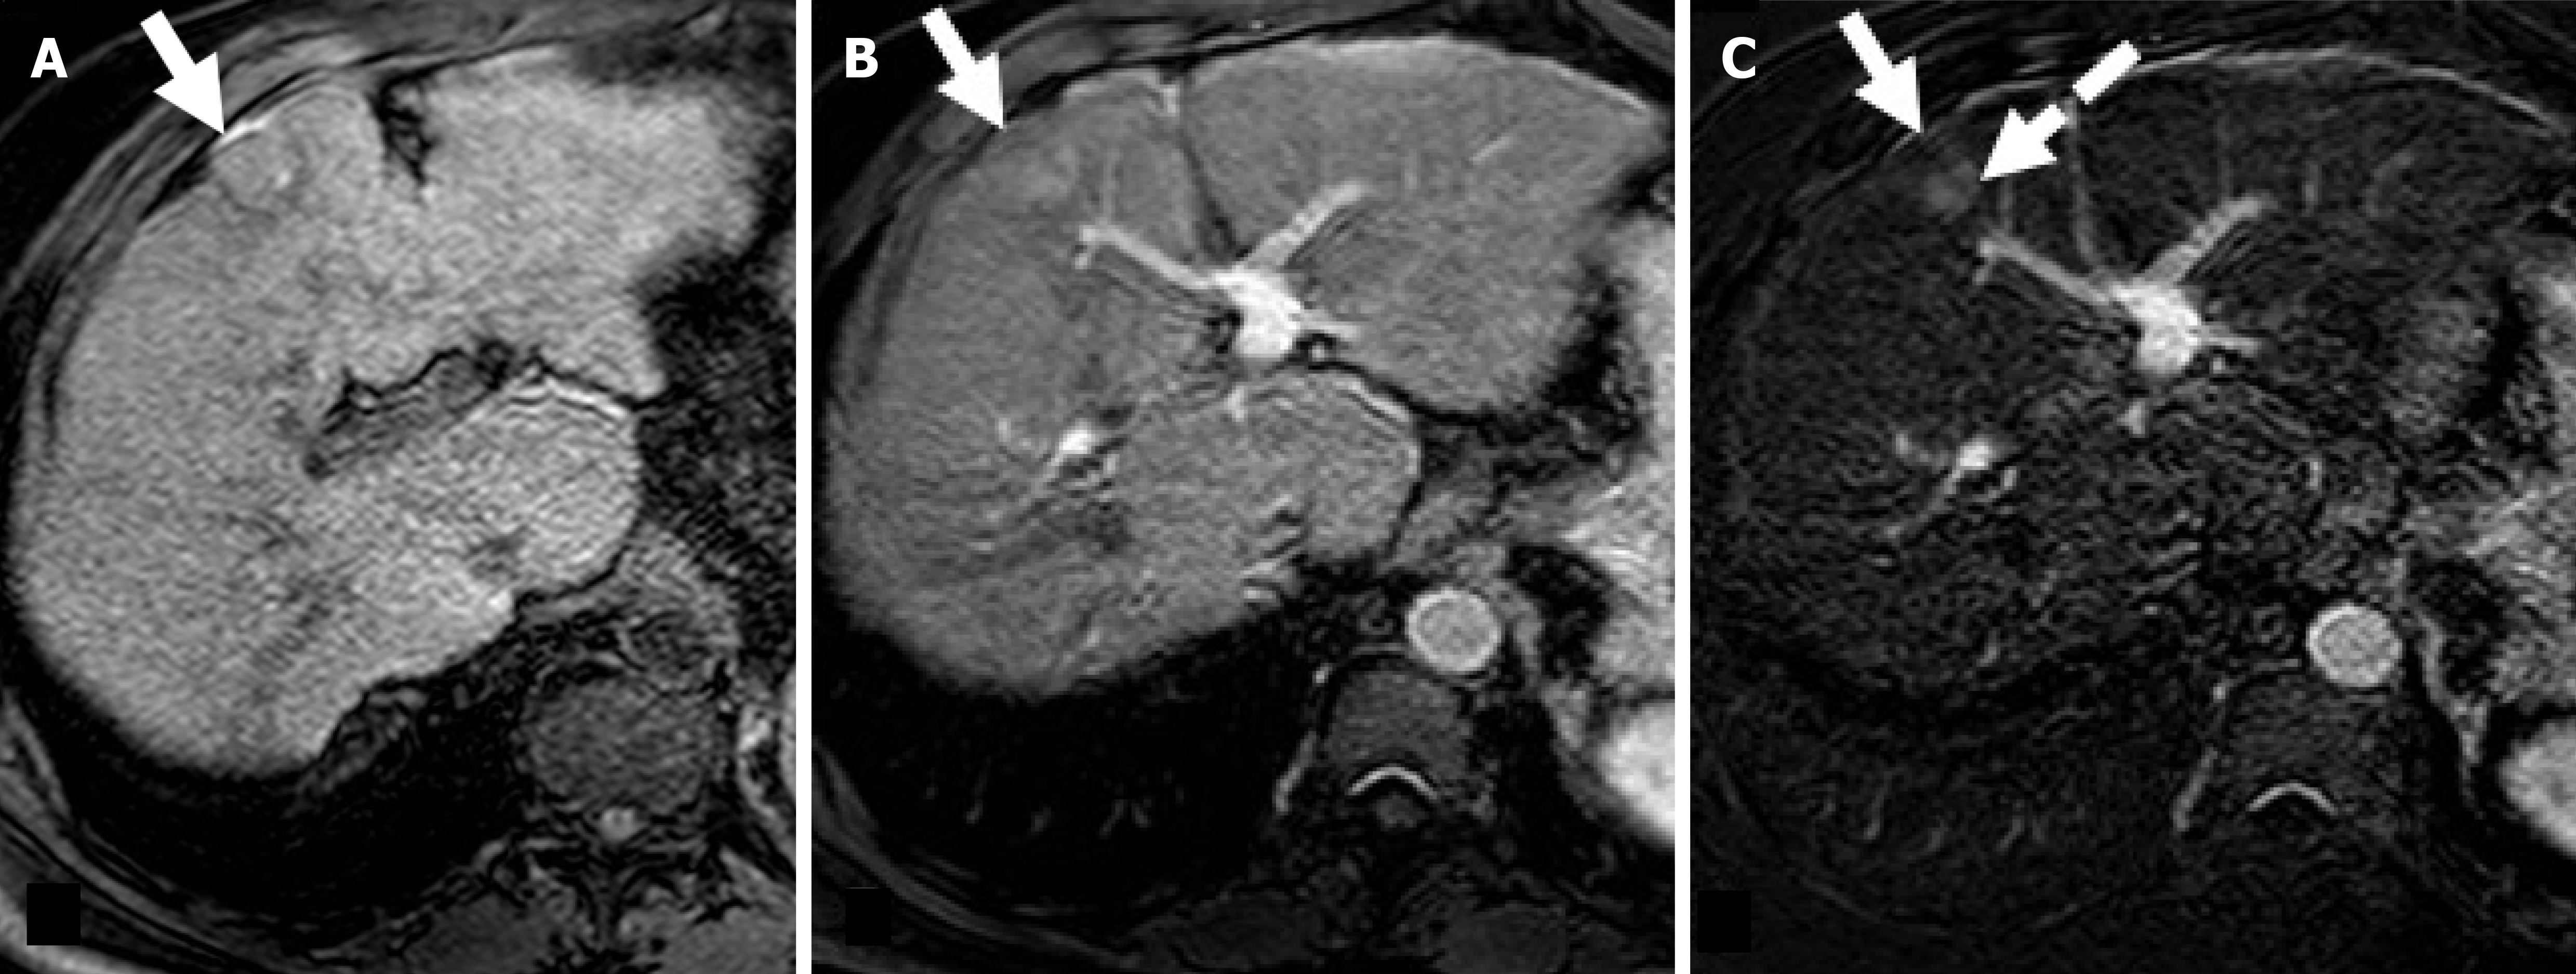

Figure 3 Residual hepatocellular carcinoma after radiofrequency ablation in a 68-year-old man with hepatitis C virus-related hepatic cirrhosis.

A: On magnetic resonance imaging obtained one month after radiofrequency ablation the treated area (arrow) shows slight hyperintensity on unenhanced T1-weighted due to coagulative necrosis; B: On corresponding hepatic arterial phase (HAP) image the treated area shows heterogenous hyperintensity; C: Subtracted HAP image shows enhancement in the posterior portion of the treated area (dotted arrow) suggesting residual tumor enhancement.